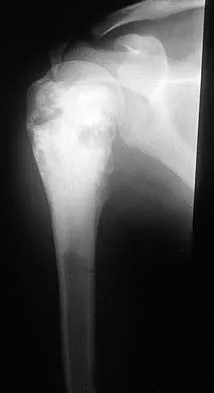

Question 26

Figure 46 shows the AP radiograph of a patient with right shoulder pain. What is the most likely diagnosis?

Explanation

Posttraumatic osteolysis of the distal portion of the clavicle is a condition that can be a complication of acute or repetitive trauma. The distal end of the clavicle is frayed and resorbed. Resorption may occur after weeks or months. The end of the clavicle may reconstitute over a period of months, or the acromioclavicular joint may remain widened. The differential diagnosis for distal clavicular erosion also includes rheumatoid arthritis, hyperparathyroidism, neoplastic destruction, cleidocranial dysplasia, and pyknodysostosis. Acutely, a type 2 acromioclavicular joint injury does not result in erosion or resorption of the clavicle. Periosteal sleeve injuries radiographically mimic acromioclavicular joint dislocation. Rickets occurs only in childhood.